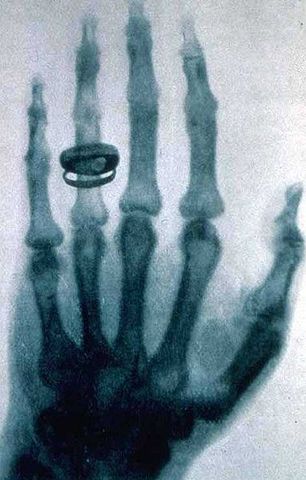

• Raig X

Raig X

Wilhelm Conrad Röntgen va ser un físic alemany descobridor de la radiació electromagnètica en longitud d'ona, origen dels raigs X.